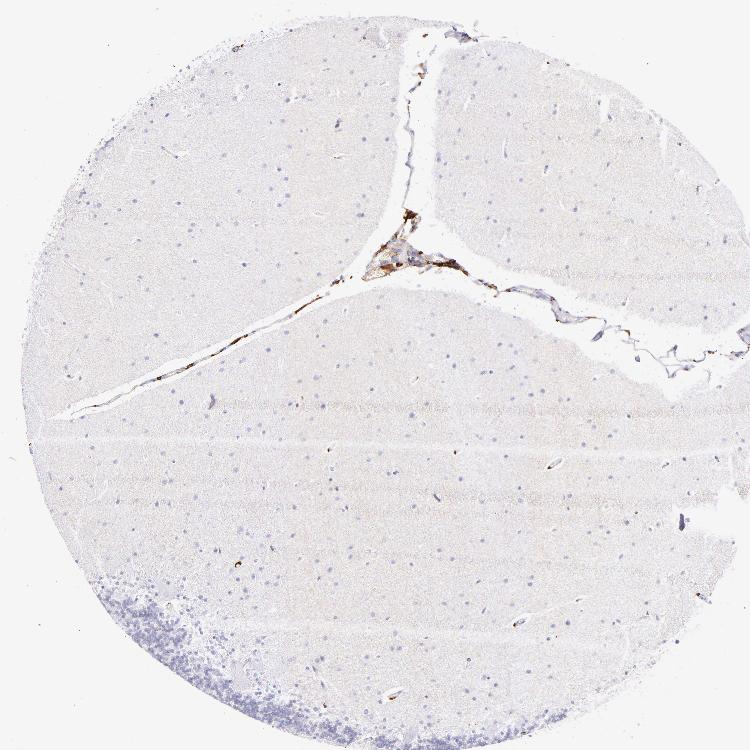

CEREBELLUM - Antibody stainingi

Antibody staining in the annotated cell types in the current human tissue is reported as not detected, low, medium, or high, based on conventional immunohistochemistry profiling in selected tissues. This score is based on the combination of the staining intensity and fraction of stained cells.

Each image is clickable and will lead to virtual microscopy that enables deeper exploration of all samples and also displays staining intensity scores, fraction scores and subcellular localization as well as patient and tissue information for each sample.

Antibody HPA046404Antibody HPA051974Antibody CAB002432

Purkinje cells LowNot detectedNot detected

Cells in granular layer Not detectedNot detectedNot detected

Cells in molecular layer Not detectedNot detectedNot detected